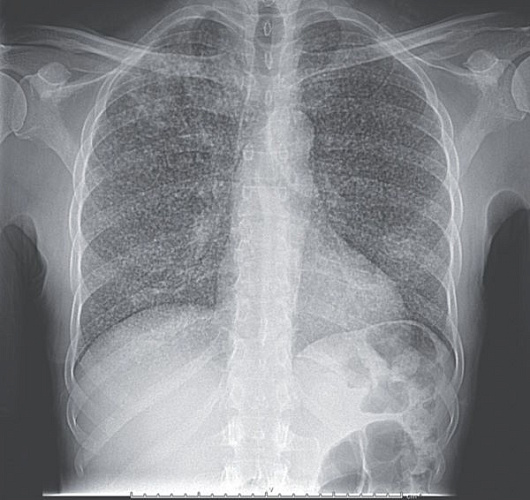

В Бурятии рассказали о «снежной буре» в лёгких

В республиканском патологоанатомическом бюро рассказали о так называемой «картине снежной бури», которую можно увидеть на рентгенограммах больных туберкулёзом лёгких.

- Этот термин описывает множественные мелкие очаговые затенения, характерные для диссеминированной формы туберкулёза, когда мелкие воспалительные изменения распределены по всей лёгочной ткани, - пояснили патологоанатомы.

В некоторых случаях, особенно на ранних стадиях туберкулёза, лёгкие могут выглядеть относительно благоприятно на рентгенограммах, потому что патология может быть локализована или не сильно выражена.

Здесь отметили, что туберкулёз может значительно изменить структуру лёгочной ткани, что становится заметно на рентгеновских снимках. Ранняя диагностика и точное исследование макроскопических изменений в лёгких помогают не только в установлении диагноза, но и в выборе адекватного лечения.